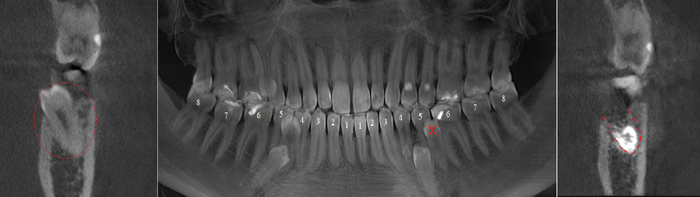

Контрольная ортопантомограмма:

Прицельный снимок:

Я согласен, что эстетика хромает. Давно пора менять временную коронку на постоянную, что улучшит результат. Но, как я говорил, все упирается в финансы.